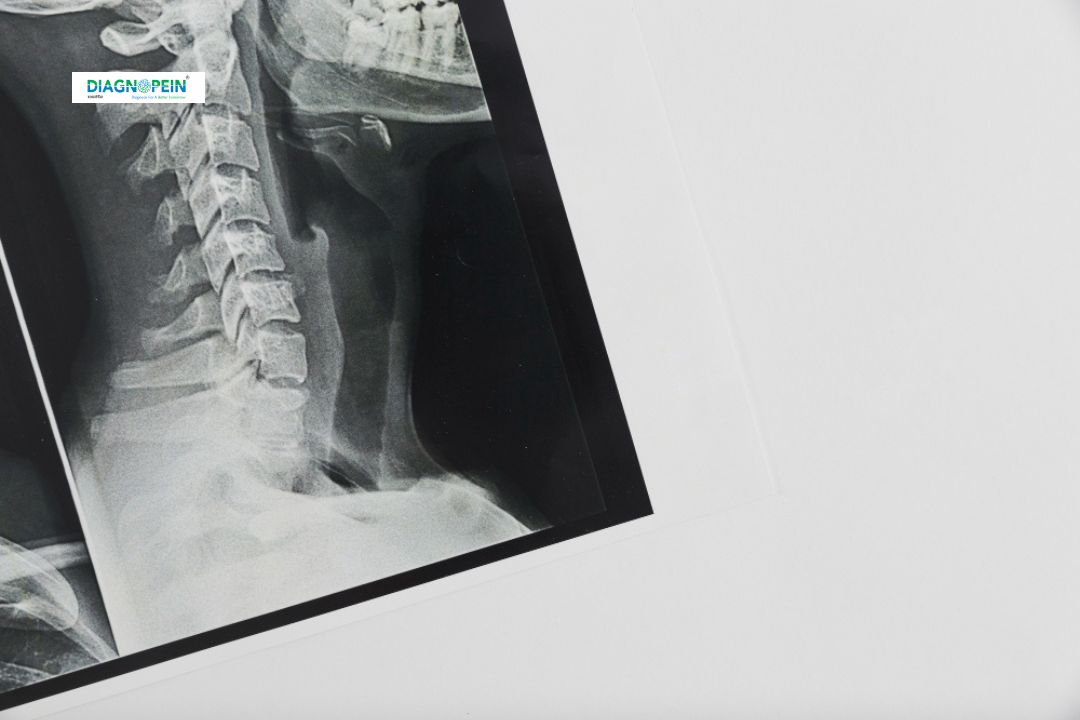

The X-Ray Cervical LAT View (Lateral View) is a diagnostic imaging test used to examine the alignment, curvature, and structural integrity of the cervical spine, which consists of the neck vertebrae. At Diagnopein, Karad, advanced imaging systems ensure precise and clear lateral cervical X-rays for accurate medical evaluation. This test plays an essential role in identifying conditions like fractures, cervical spondylosis, spinal misalignments, or other neck bone abnormalities.

This imaging method is non-invasive, quick, and safe for patients of all ages. The lateral view allows doctors to see sideways images of the neck region, revealing the vertebrae from C1 to C7 in detail.

4. The lateral (side) view image captures the full cervical spine from C1 to C7.

The X-Ray Cervical LAT View helps visualize several key parameters such as:

1. Alignment and curvature of cervical vertebrae (C1–C7)

2. Joint space narrowing or abnormal spacing

3. Bone formation, osteophytes, or spondylotic changes

4. Cervical lordosis angle and vertebral body height

5. Prevertebral soft tissue thickness

Each of these parameters assists in evaluating spinal health accurately, guiding doctors in determining suitable treatment or therapy options.